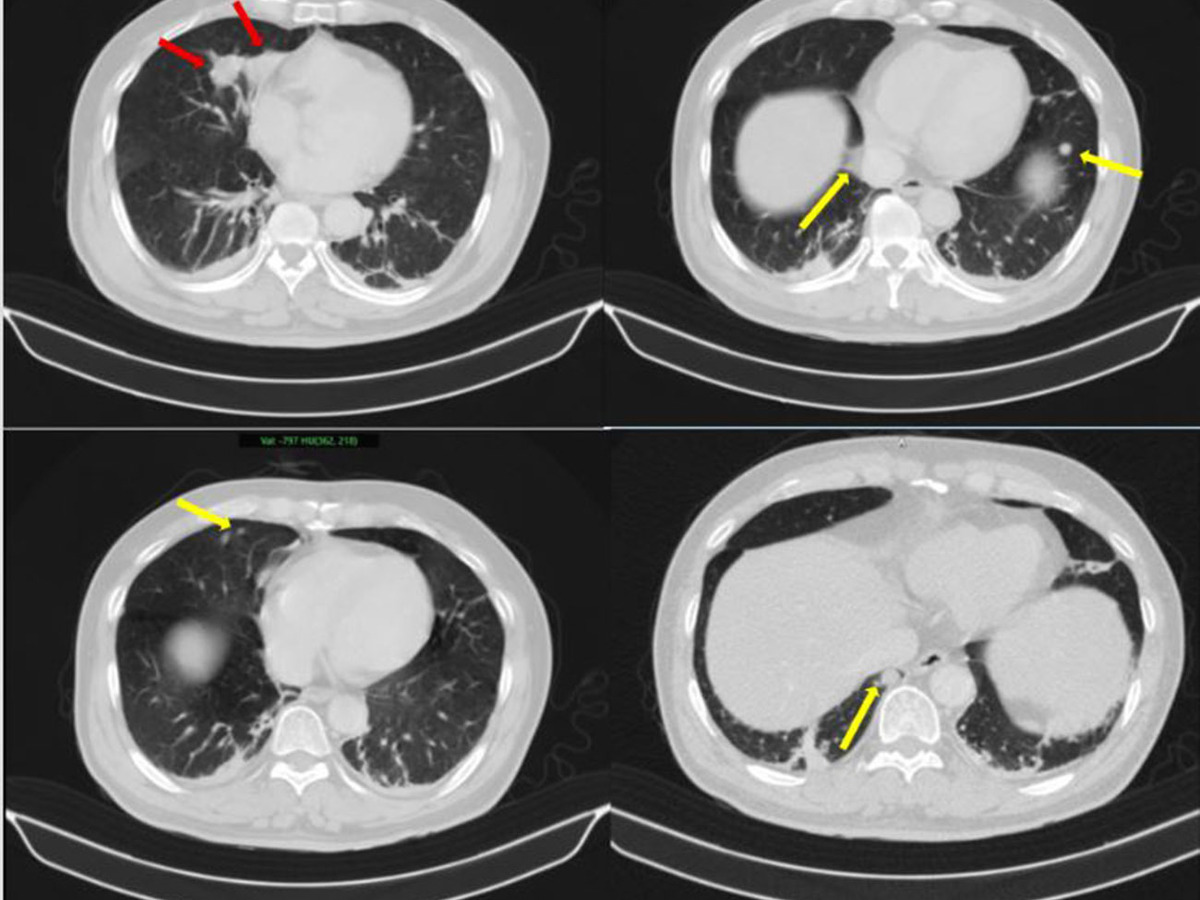

Hình ảnh dày tuyến thượng thận phải tạo nốt có kích thước 19 x 17 mm (Ảnh: BV Bạch Mai)

Kết quả sinh thiết và phân tích mô bệnh học kết hợp hóa mô miễn dịch giúp làm rõ: khối u phổi là ung thư biểu mô tuyến của phổi, trong khi khối u tuyến tiền liệt là ung thư biểu mô tuyến với điểm Gleason 9 - thuộc nhóm nguy cơ cao. Hai loại ung thư này có nguồn gốc hoàn toàn khác nhau, không phải di căn chéo.